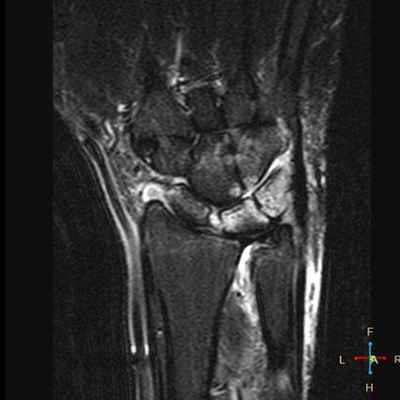

Повреждение менисков и капсульно-связочного аппарата коленного сустава. «Несчастная триада». Механизмы травмы. Клиническая картина и диагностика. Методики хирургического лечения.

· - МРТ – позволяет оценить степень деструкции мыщелка, являясь важной составляющей в решении вопроса о хирургическом лечении.

Несчастная триада относится к травме растяжения связок, в которой задействованы три структуры колена. Этими структурами являются медиальная коллатеральная связка, передняя крестообразная связка и медиальный мениск.